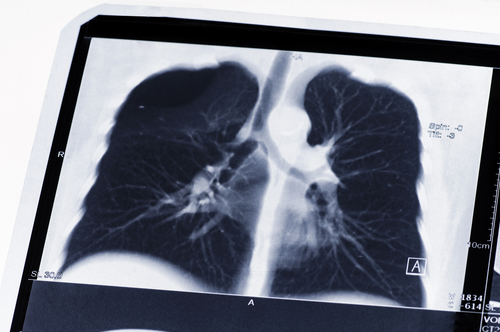

According to physicians at the Medical College of Georgia at Augusta University, a portable ultrasound can help nephrologists better detect fluid in the lungs of patients with end-stage kidney disease. The trick is to know where the fluid is and how much needs to be removed, said Dr Omar Saleem, and accumulation in the lungs can lead to complications like heart failure and high blood pressure. When it comes to diagnosing "wet lungs," the standard has been listening for chest crackling sounds with a stethoscope and measuring blood pressure - more fluid on the lungs prevents oxygen from being absorbed into the bloodstream.

"But that's quite subjective," he said. "For instance, sometimes you can't hear the crackling. That's why the ultrasound adds to the physical exam." He examined 24 ESKD patients and as part of the normal physical exam, he placed the ultrasound probe on the patients' chests to get a good view of the lungs. If there was fluid, he would see B-lines, which are actually reflections of the water in the lungs that appear as long, vertical white lines on an ultrasound. The higher the number of B-lines and the more intense, or bright, they were, the more fluid was present.